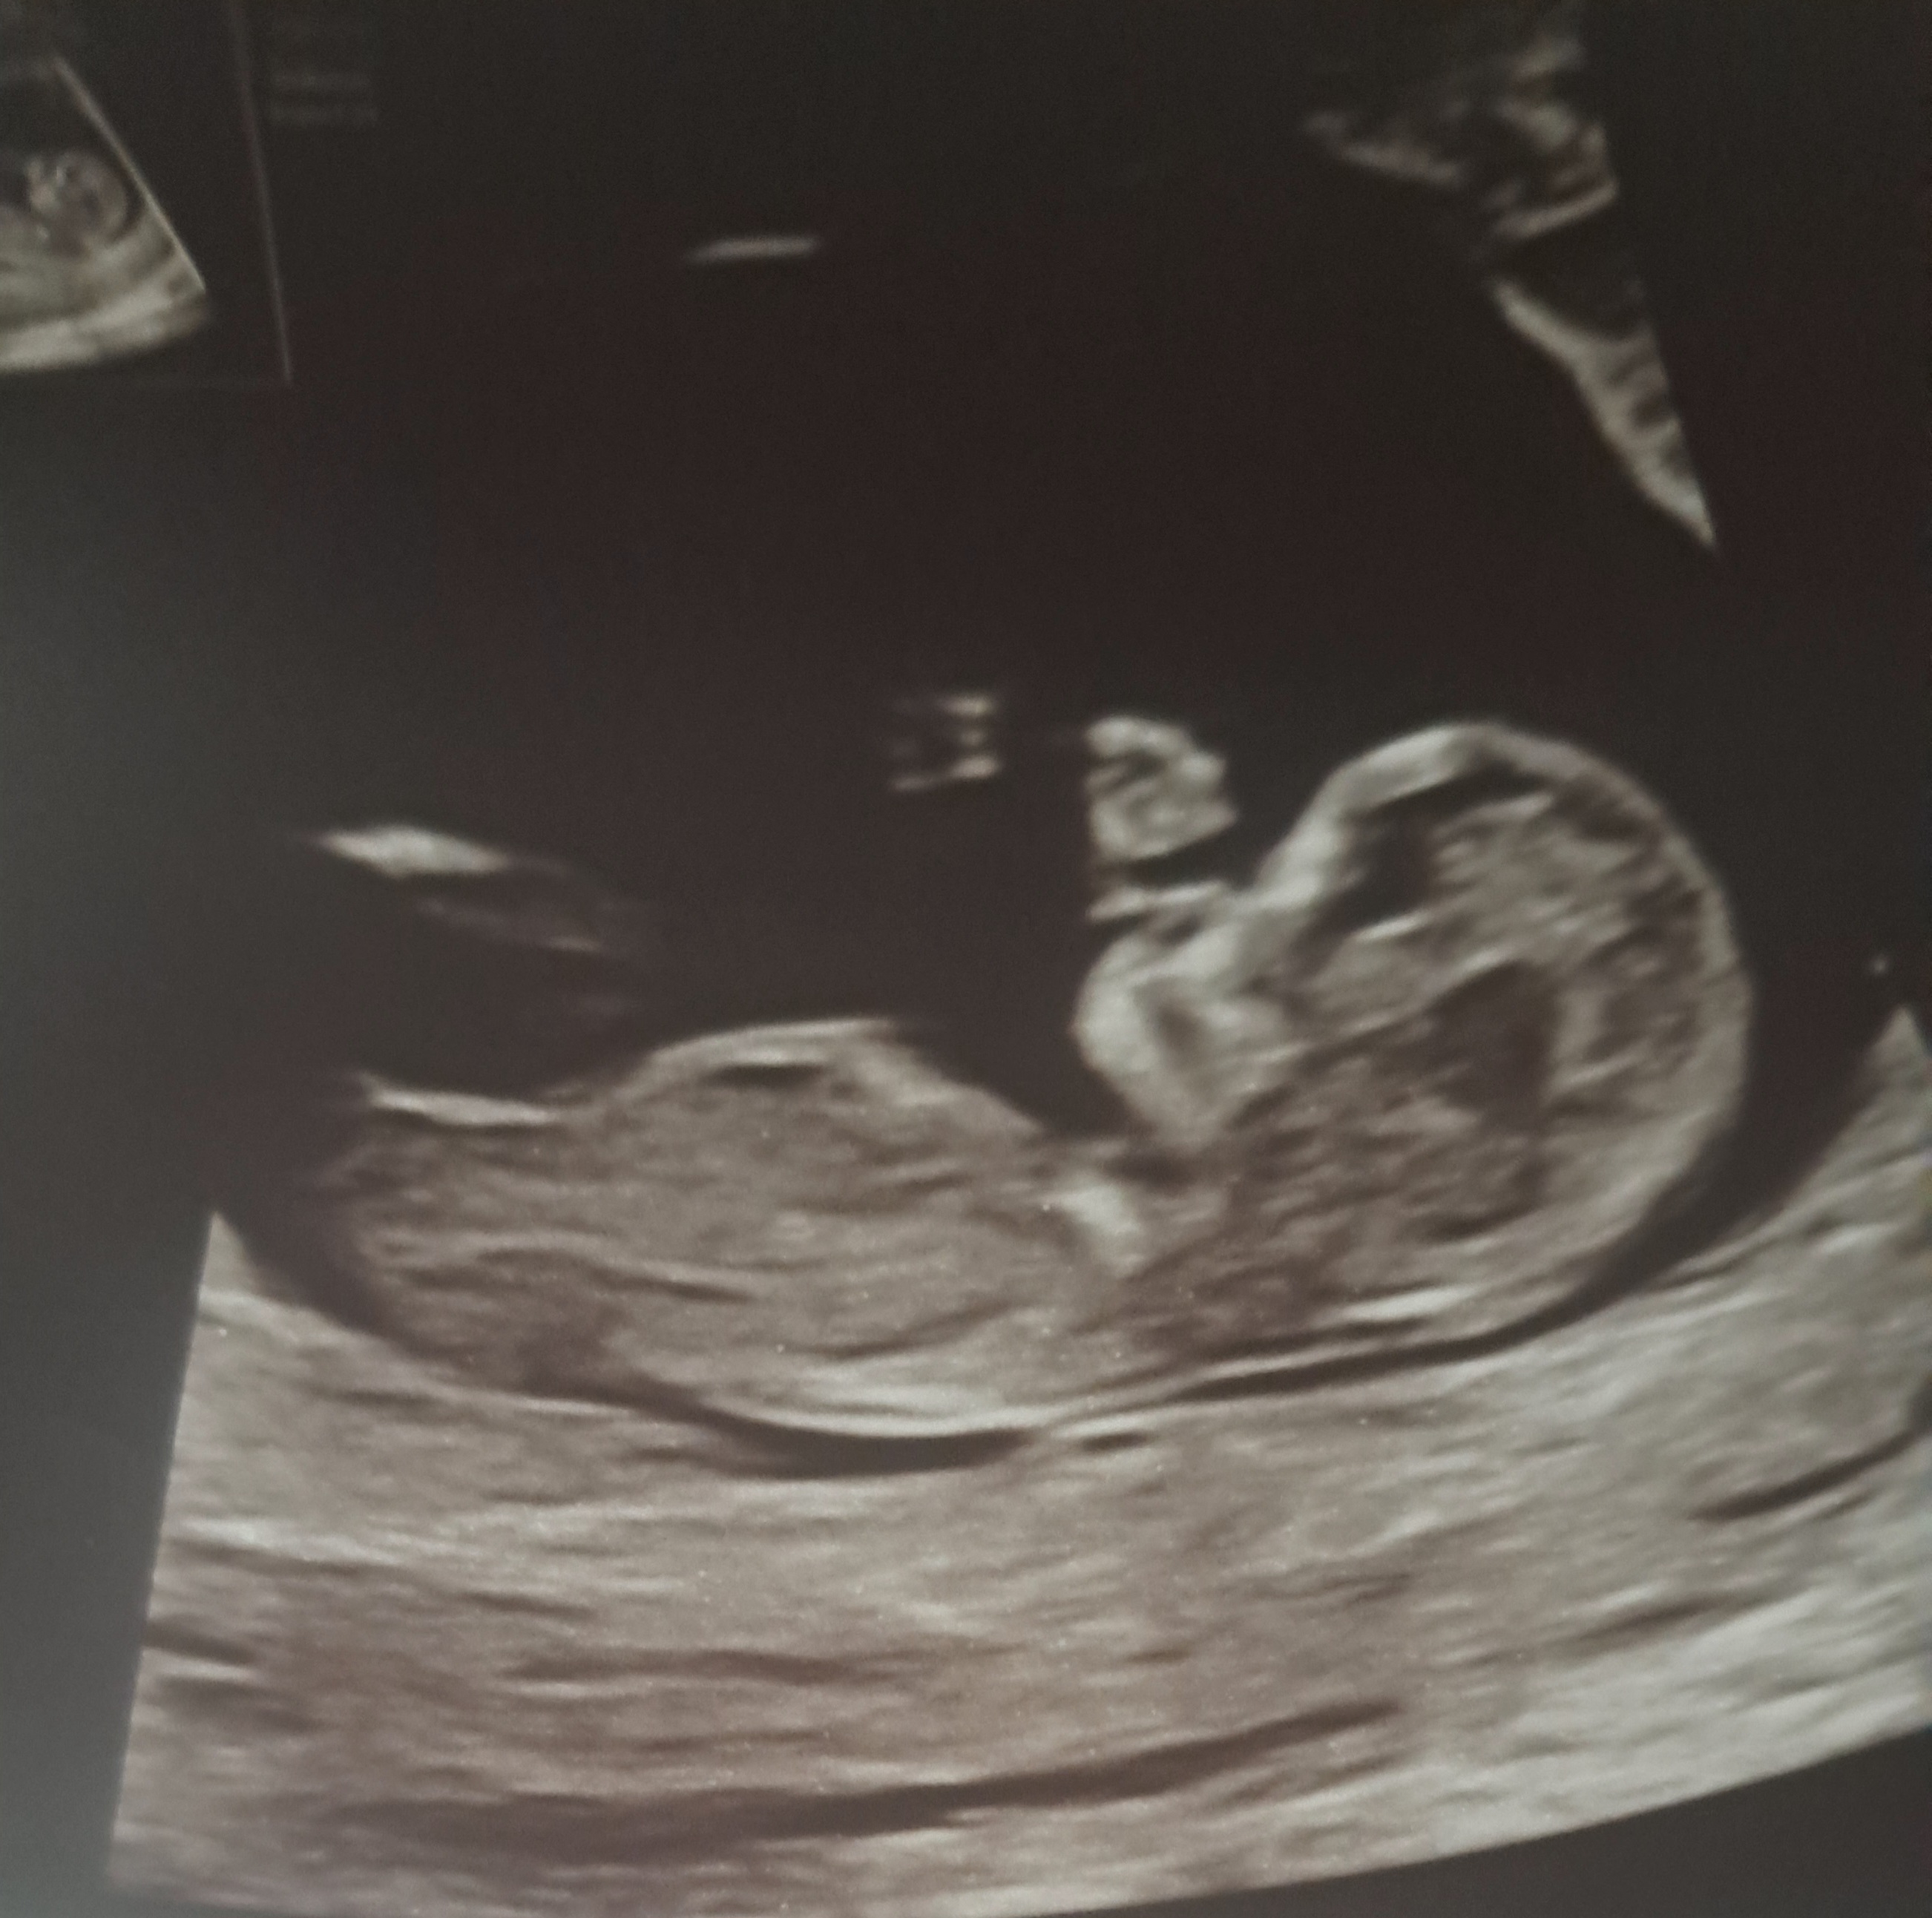

Jestem po pierwszych prenatalnych. Pani dr. pokazala mi wyrostek plciowy ktory lezal plasko…wiec na 75% dziewczynka

zobaczymy czy potwoerdzi sie na polowkowym ![]()

My dowiedzieliśmy się w 13 tc i teraz czekamy na córeczkę, zostało nam 6 dni do terminu ![]()

Moim zdaniem to jeszcze troszkę za wcześnie